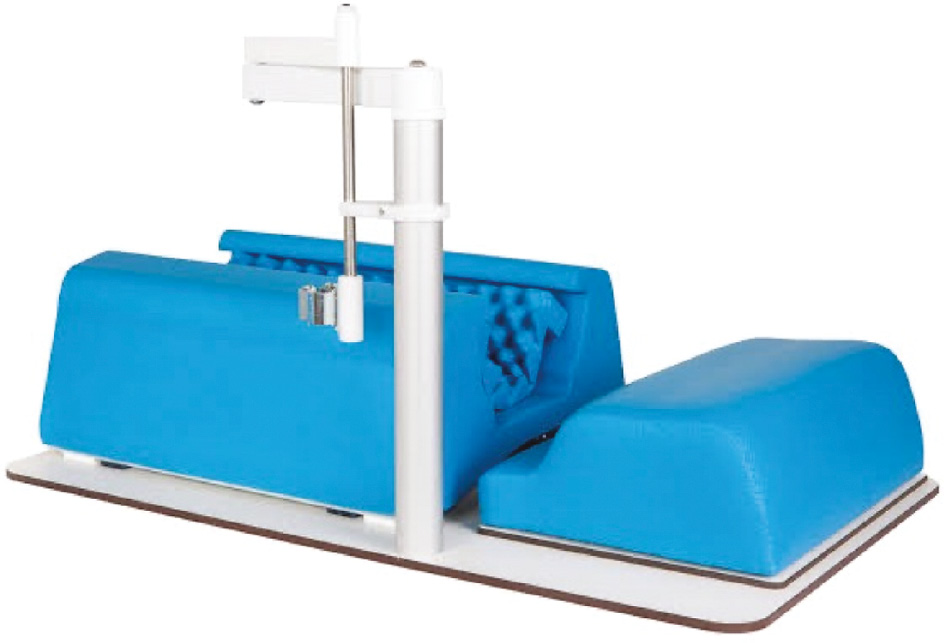

Using a Graf table (Figure 7) with a phantom baby (Figure 8), one can replicate all exam steps. By following all the steps listed above, on the simulation baby in the lateral decubitus position (Figure 9), one can acquire the skills to understand ultrasound evaluation of morphology. Limitations of using the phantom baby is that it does not allow for a dynamic exam and, although it allows understanding of normal anatomy, the phantom does not although the trainee to identify and measure pathologic findings (Figure 10). Once the trainee is comfortable and demonstrates proficiency with the phantom baby in the Graf table, we recommend practicing the exam with the phantom outside the positioner (Figure 9).

Figure 7. Graf Table.

- Graf table: $2030 U.S. (from 1800E), Mexican version $800 U.S.